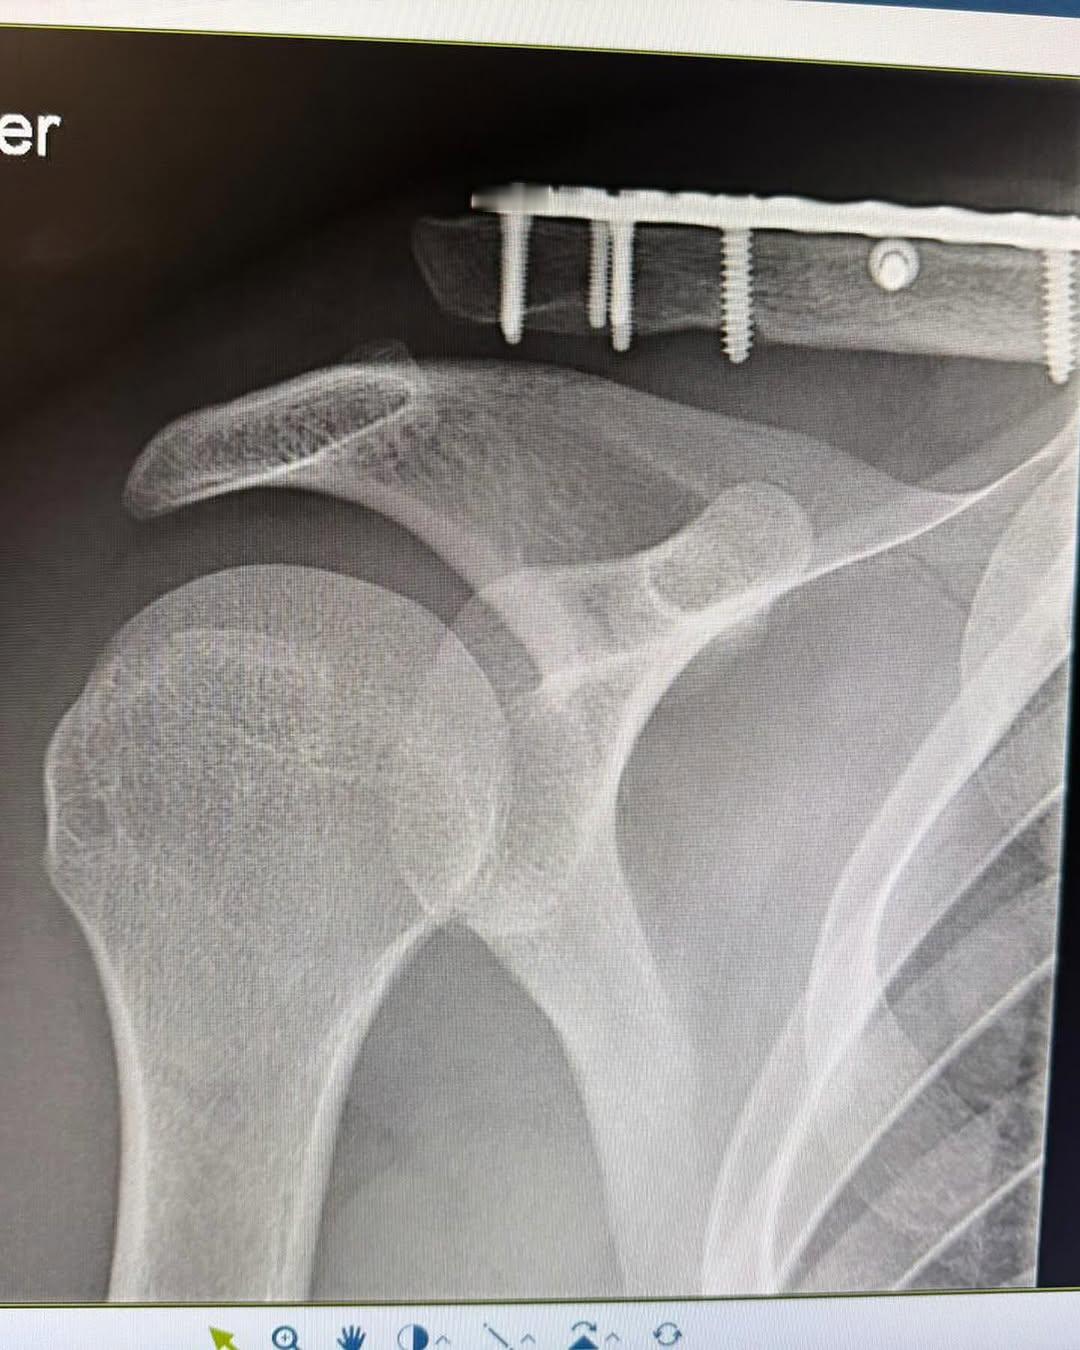

本周五,埃菲内普尔将在布拉班特之箭赛上演赛季首秀。去年冬天遭遇开门杀,锁骨等多处骨折的巴黎奥运冠军非常感慨,在个人社媒上写了很长一段,说这是他人生最艰难的时刻,一度陷入低谷,对自己的未来充满怀疑,然后感谢了妻子、父母、亲朋、医护人员的帮助。希望接下来的比赛也能平安吧,起码是比赛一大看点